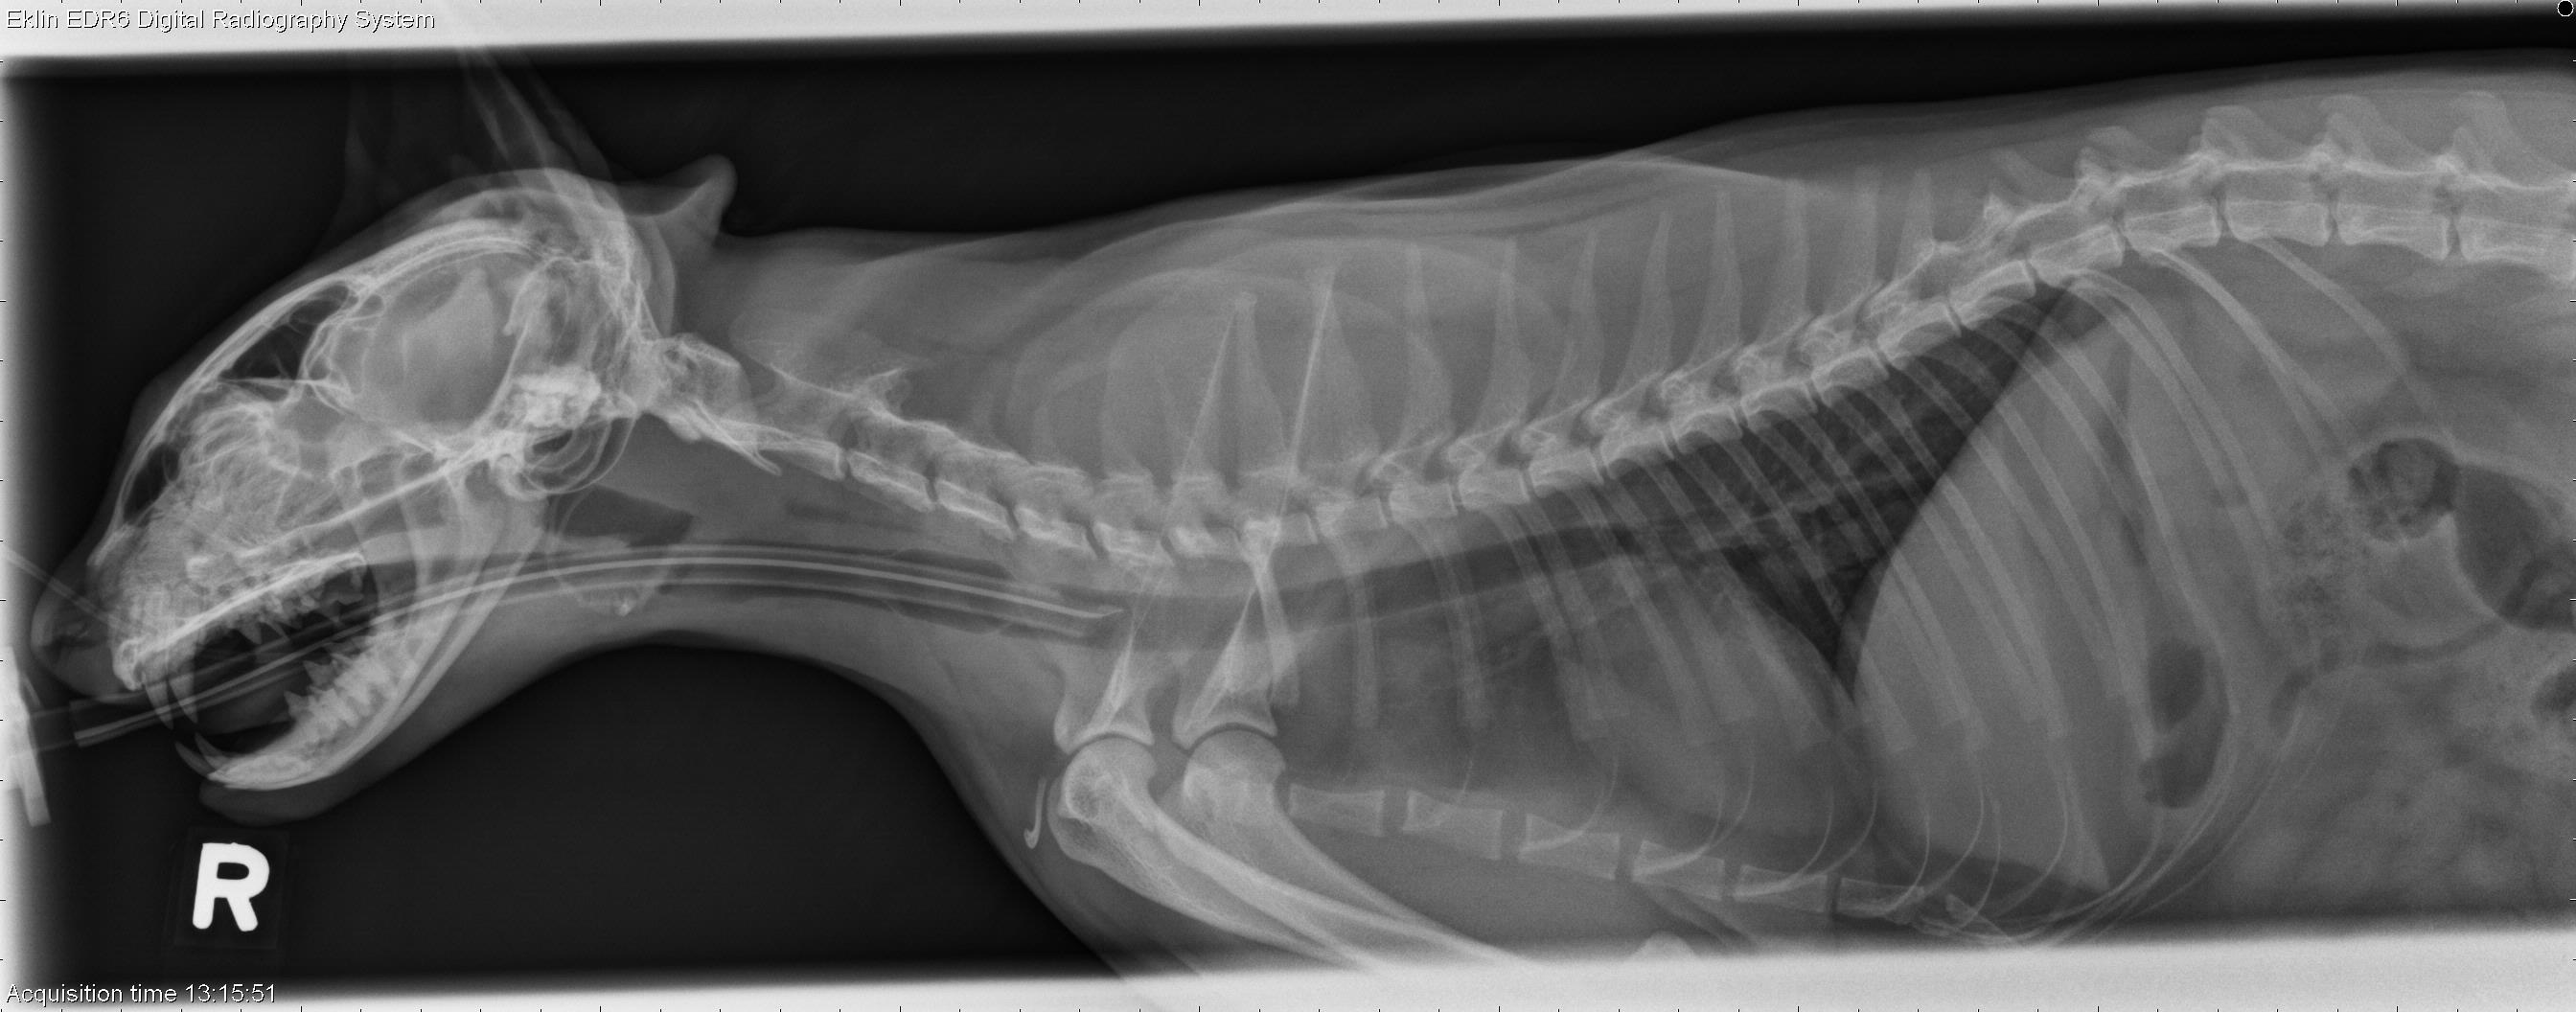

From www.veterinaryradiology.net

2 year old DSH cat Laryngeal Polyp Cat Laryngeal paralysis, a disorder of the upper airway, is rare in cats. Cats with laryngeal paralysis (lp, n=14), laryngeal neoplasia (n=10), laryngeal inflammation (n=6), or. Nasal polyps, also known as nasopharyngeal polyps, are benign, fleshy masses that develop in the nasal passages of a cat. A variety of disorders can affect the urt of cats. Chronic idiopathic rhinosinusitis (noninfectious, inflammatory). Laryngeal Polyp Cat.